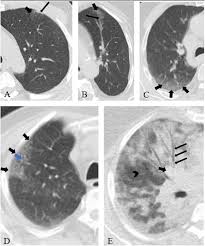

Diagnostic Accuracy Of North America Expert Consensus Statement On Reporting Ct Findings In Patients Suspected Of Having Covid 19 Infection An Italian Single Center Experience Radiology Cardiothoracic Imaging

Diagnostic Accuracy Of North America Expert Consensus Statement On Reporting Ct Findings In Patients Suspected Of Having Covid 19 Infection An Italian Single Center Experience Radiology Cardiothoracic Imaging from pubs.rsna.org